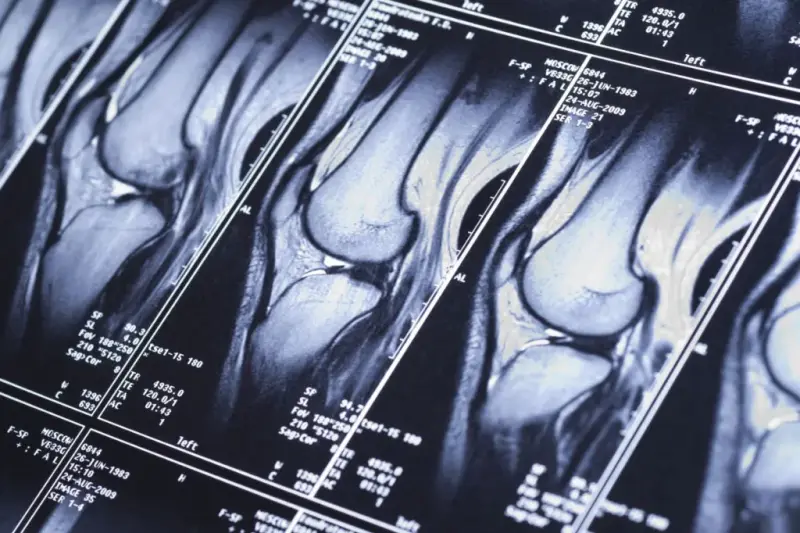

Diagnoza uszkodzenia więzadła krzyżowego przedniego wymaga dokładnego wywiadu medycznego oraz badań obrazowych, które potwierdzą stopień uszkodzenia więzadła. Podstawowym narzędziem diagnostycznym jest rezonans magnetyczny (MRI), który umożliwia precyzyjne uwidocznienie struktur kolana, takich jak więzadła krzyżowe, łąkotki czy chrząstka stawowa. Jeśli interesuje Cię rezonans magnetyczny Warszawa, bez skierowania to szybki termin możesz zrealizować prywatnie, na przykład w placówce MRI Diagnostyka. Badanie kolana rezonansem magnetycznym pozwala na ocenę struktury ACL oraz rozpoznanie innych możliwych uszkodzeń stawu kolanowego. Rezonans magnetyczny jest szczególnie ważny, gdy istnieje podejrzenie dodatkowych urazów, jak uszkodzenie łąkotki przyśrodkowej lub więzadeł pobocznych, które mogą wymagać innego leczenia. W niektórych przypadkach diagnostyka obejmuje również badanie USG kolana, szczególnie gdy badanie MRI jest niedostępne lub potrzeba natychmiastowej oceny.